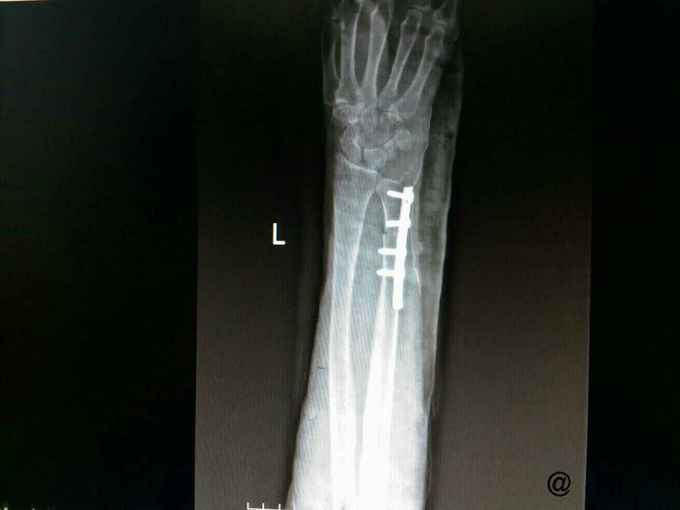

腕关节X片可见尺骨远端囊性变。

考虑患者生活方便先行左侧尺骨短缩术